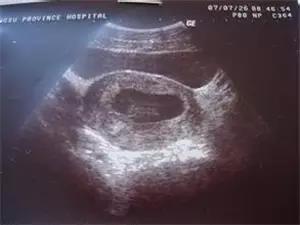

原則上在孕40天時(shí),我們就可以通過陰道超聲,觀察到宮內(nèi)的孕囊,在孕45天時(shí),看到胚芽和胎心搏動。

如果此時(shí)血清HCG >1000 IU ~ 1500 IU,B超還沒有看到宮內(nèi)的典型孕囊,異位妊娠的可能性>95%,需要留院觀察,動態(tài)超聲檢查,看輸卵管和其它部位是否出現(xiàn)孕囊和胎心。

因此,在這個(gè)懷孕階段,不要拒絕超聲檢查,即使HCG的檢測水平只有幾百單位,B超沒有見到宮內(nèi)孕囊,都要密切觀察是否宮外孕可能。

胚胎停止發(fā)育的診斷比起宮外孕的診斷要容易得多,早孕期血清HCG水平低下,翻倍試驗(yàn)異常,B超觀察到宮內(nèi)有孕囊,有的也看到胚芽和卵黃囊,但在孕45~50天還沒有見到胎心搏動,延長觀察了1~2周,還未見胎心。

此時(shí)超聲的診斷具有最可靠的價(jià)值,其它HCG和孕酮水平測定都沒有診斷意義了,不建議盲目保胎,更沒有必要再繼續(xù)使用黃體酮或HCG制劑。